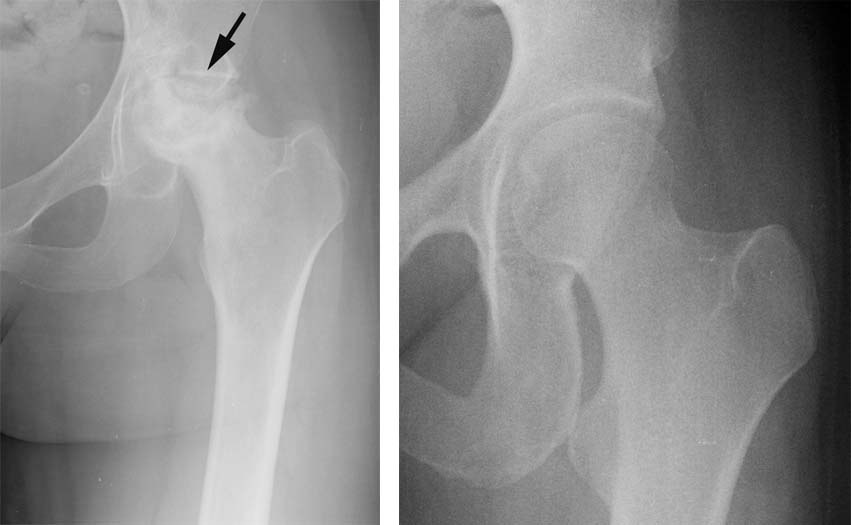

The following case is an illustration of the steps involved in a total hip replacement performed in a 29 year old female with severe avascular necrosis of the femoral head and secondary arthritis.

1.This patient's hip radiograph (left) demonstrates the advanced avascular necrosis of the femoral head. This is shown as flattening and fragmentation of the upper aspect of the femoral head. At the time of the radiograph, we also notice that she has developed flattening at the edge of the hip socket (arrow). A normal hip radiograph is shown immediately below the patient's hip radiograph.